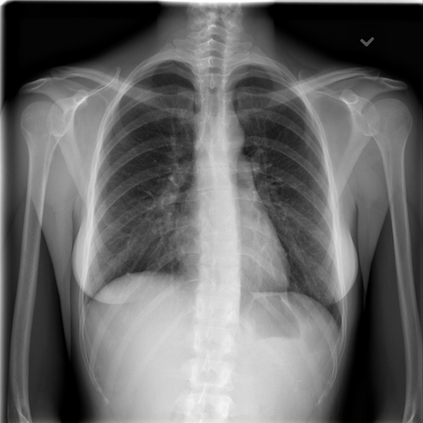

Tuberculosis remains a critical global health issue, particularly in resource-limited and remote areas. Early detection is vital for treatment, yet the lack of skilled radiologists underscores the need for artificial intelligence (AI)-driven screening tools. Developing reliable AI models is challenging due to the necessity for large, high-quality datasets, which are costly to obtain. To tackle this, we propose a teacher--student framework which enhances both disease and symptom detection on chest X-rays by integrating two supervised heads and a self-supervised head. Our model achieves an accuracy of 98.85% for distinguishing between COVID-19, tuberculosis, and normal cases, and a macro-F1 score of 90.09% for multilabel symptom detection, significantly outperforming baselines. The explainability assessments also show the model bases its predictions on relevant anatomical features, demonstrating promise for deployment in clinical screening and triage settings.